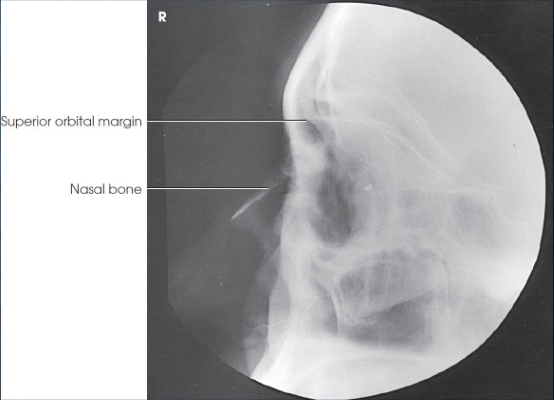

Lateral nasal bones

patient position:

upright or recumbent anterior oblique position

MSP parallel with IR

part position:

IPL perpendicular

flex neck to place IOML parallel to transverse axis of IR

respiration suspended

CR:

perpendicular

enters 1 inch distal to nasion

collimation:

extends from the glabella to 1 inch inferior to the acanthion and ½ inch beyond the tip of the nose

should be no larger than 3 × 3 inches

both sides done for comparison

Lateral nasal bones image criteria

shows:

nasal bone and soft tissues of the nose

anterior nasal spine

frontonasal suture

no rotation

Lateral orbits

patient position:

upright or recumbent anterior oblique position

part position:

outer canthus of affected eye adjacent and centered to IR

adjust patient’s head to place MSP parallel with IR

IPL perpendicular to IR

flex neck to place IOML perpendicular to front edge of IR

respiration suspended

CR:

perpendicular through outer canthus

Lateral orbits image criteria

entire orbit(s)

no rotation

superimposed orbital roofs

close beam restruction centered to orbital region